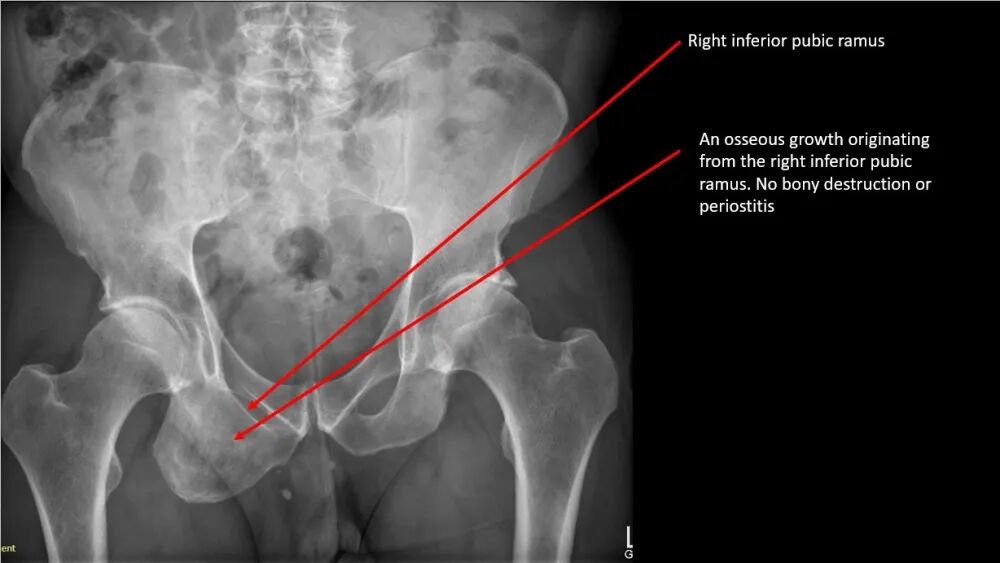

• 行骨盆X线检查——见下图。

发生于骨盆者罕见,约占5%。耻骨支骨软骨瘤极为罕见。

• 本例骨软骨瘤的位置不太可能引起患者症状。该病变为偶然发现,采取保守治疗。